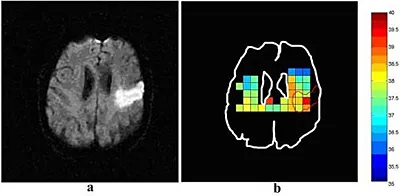

BRIC uses Magnetic Resonance Spectroscopic (MRS) to collect data used to estimate temperature on a voxel by voxel basis. OverviewPurposeDetailContactDr Michael ThrippletonRelevant linksEdinburgh Imaging Facility WGHStrokeBrain & nervous system Temperature estimation is based on the known temperature dependence of the water resonance frequency. The dependence is very small at 0.01ppm per degree C, but can nevertheless be detected in MRS data sets.Researching activity measuring heat in brain tissues:Edinburgh Imaging Facility WGH carried out retrospective analysis of MRS data from 40 stroke patients. By combining data from several voxels from each patient, we showed that regional temperatures vary within the ischaemic lesion. Referring to the diagram below, the acute ischaemic stroke lesion is marked in red (left hand side), which shows the corresponding temperature within the lesion being variable. Image Above figure: (a) diffusion-weighted image and (b) corresponding temperature map of a patient with an acute ischaemic stroke lesion in the left parietal region. In (b), the lesion outline is shown in red. Temperature scale in degree C.Researching activity measuring coolness in brain tissues:Members of the EIF WGH team have also been keen to work alongside the Brain Cooling team, to assess whether reducing the temperature of injured brain tissue can help protect it from further damage. Prof Macleod is leading a trial testing a new device, Brain Cool Dignicap. This is a silicon cap and neck collar with fluid channels of cooling fluid which lowers the scalp temperature and blood in the neck (Fig 3). This is already a technique well established for the prevention of chemotherapy induces hair loss. As therapeutic hypothermia is a promising treatment for stroke and traumatic brain injury, this trial hopes to be able to cool deeper brain tissue in awake volunteers. If successful this could potentially lead to brain-cooling treatment being available in ambulances.Video clip: Image Brains cooled for Edinburgh University stroke researchAbove: Cooling cap and neck collar on a volunteer.Additional information can be gained by clicking here:Brain cooling projectStaff contactIf you wish further information on the above activities, please contact Dr Michael Thrippleton:Dr Michael Thrippleton This article was published on 2024-08-22